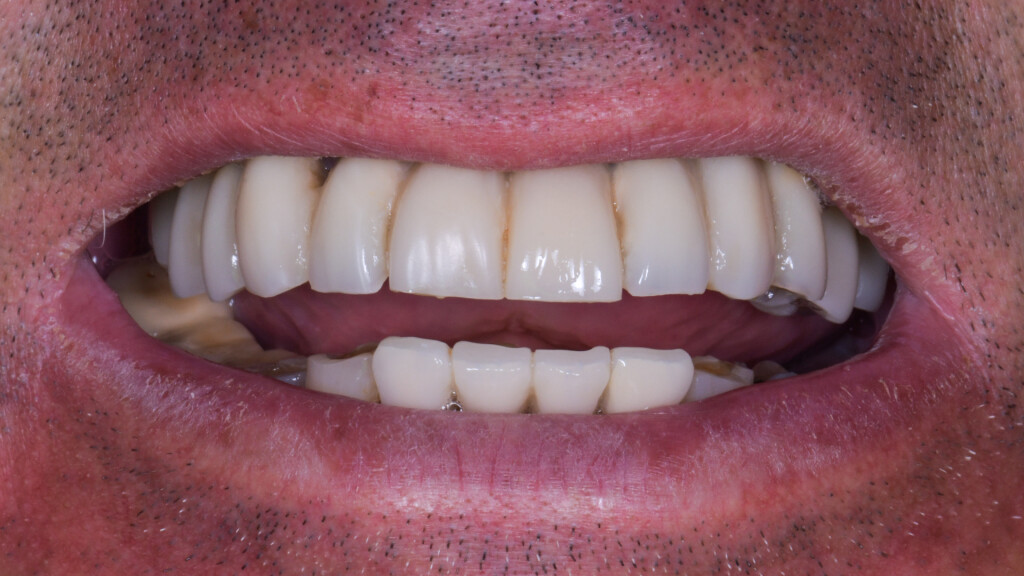

EXTRA

EXTRA2